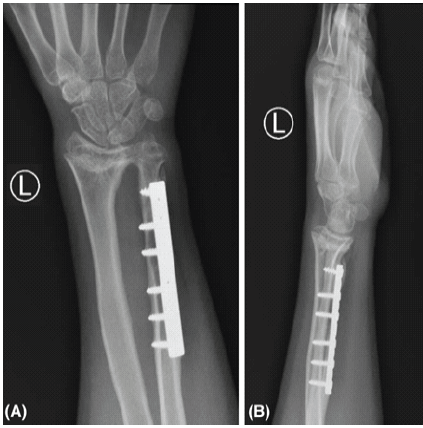

The k-wires were bent and cut before closure of the wound, which was done subcuticularly. The closure was done with vicryl 2–0 for the subcutaneous tissue and monocryle 3–0 subcuticular for the skin. The patient was positioned on a backslab with near full forearm supination position post-correction. The boy had an uneventful post-operative course, and he was evaluated 2 weeks post-operative, which showed a well-healed surgical wound, then 8 weeks post-operativelyK-wires and backslab were removed. After removal of K-wires and backslab, the patient was referred to physiotherapy early on treatment with gradual supervised sessions from regaining range of motion to full-weight-bearing instruction and increasing the hand/wrist power and strength. He continued follow-ups in our pediatric orthopedic clinic after 2, 4, and 8 months consecutively after removal of the slab. Clinically, the patient was off-pain and had increased ROM of the wrist with almost full forearm supination, full forearm pronation, full wrist radial and ulnar deviation, and near full wrist flexion and extension in the final follow-up at 1 year post-surgical intervention (Table 1). Radiologically, the ulnar bone was fully healed and well-aligned radioulnar and wrist joint, and carpal bones (Fig. 3).

Figure 3: (a) Final postoperative left wrist anteroposterior X-ray. (b) Final post-operative left wrist lateral X-ray.